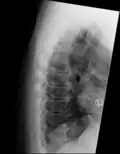

![]() | |

DISH in an 80 year old female, also with T11 fracture. | |